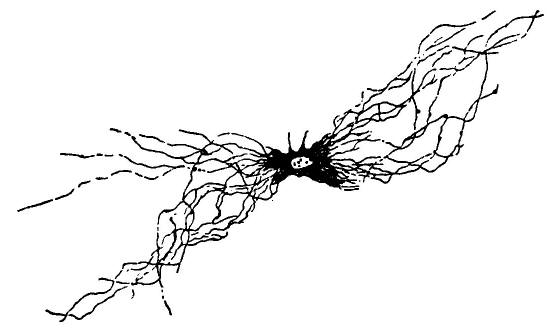

| 20. | Complexity of cell of the central nervous system | 131 |